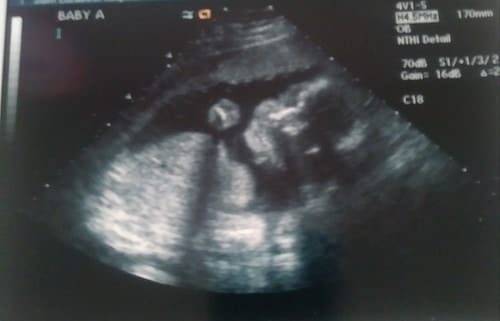

Ultrasound Photos at 26 Weeks Pregnant With Twins